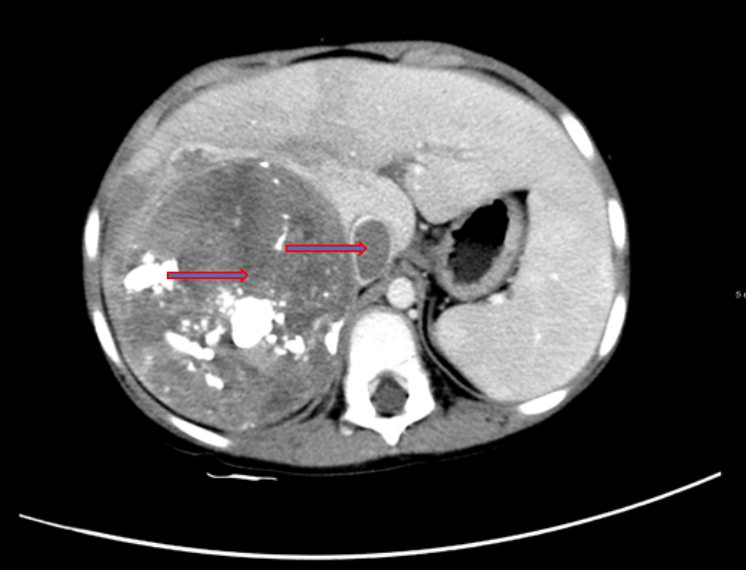

胸部+上下腹部CT检查:肝右叶增大,右后叶可见软组织影,约9.8×9.0×8.6cm,边界欠清晰,密度不均匀,其内可见钙化灶,增强扫描不均匀强化,考虑肝母细胞瘤;下腔静脉内低密度影,考虑瘤栓;双肺多发结节影,长径约2~11mm,边界清晰,考虑转移瘤;前纵膈软组织影,考虑未退化胸腺组织。

图1 胸部+上下腹部CT